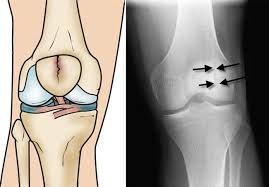

A knee fracture occurs when one or more bones forming the knee joint sustain a break due to trauma or excessive stress. This may involve the patella, distal femur, or proximal tibia, each affecting knee movement differently. Such injuries can disrupt the natural alignment of the joint and restrict normal movement.

Accurate diagnosis is the foundation of successful knee fracture treatment. Patients undergo detailed clinical examination supported by imaging studies such as X-rays or advanced scans when needed. Dr. Aniruddha Deshmukh carefully interprets diagnostic findings to assess fracture severity and joint involvement. Early and accurate evaluation ensures timely intervention and improves overall recovery outcomes.